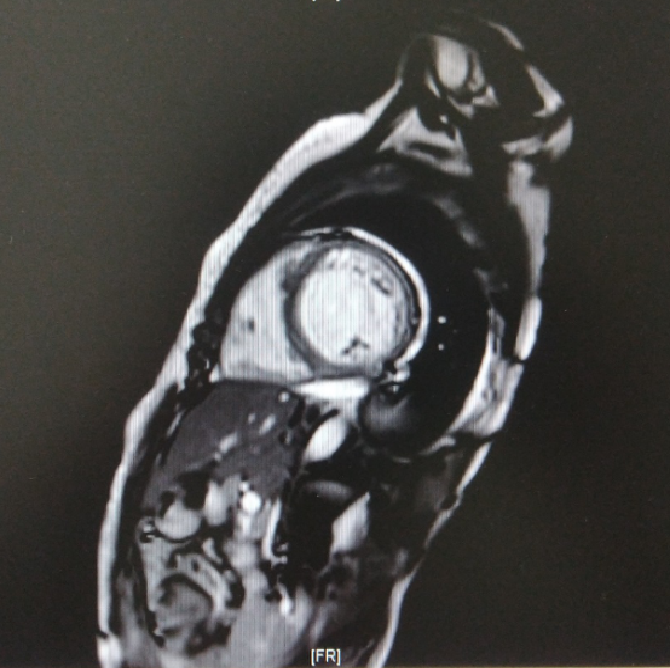

• 2021-04-07磁共振增强:心肌受累疾患,左心功能不全,扩张型心肌病可能性大,左室侧壁心尖致密化不全,室间隔及左室壁(包括增粗肌小梁)多发纤维化,须与炎症后心肌病等鉴别。